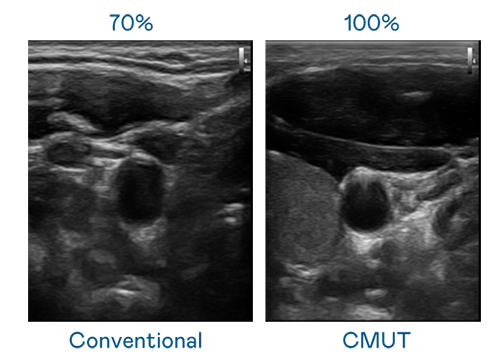

CMUT 技术是一种用电容式微机电元件来产生超音波讯号的技术。与传统 PZT 压电式技术相比,CMUT 频宽增加 30%,更宽频的超音波讯号让影像解析度大幅提升,是实现高影像品质医疗超音波扫描、促进精准医疗发展的关键技术。

大频宽带来超清晰影像

超音波影像的解析度高低,首先取决于探头能发出的讯号频宽。BB贝博艾弗森 CMUT 可提供高清晰的超音波讯号,提供高频宽、高灵敏度、影像纹理细节更高的超音波影像,协助医护人员缩短影像判读时间及利用精准的医疗影像进行诊断。